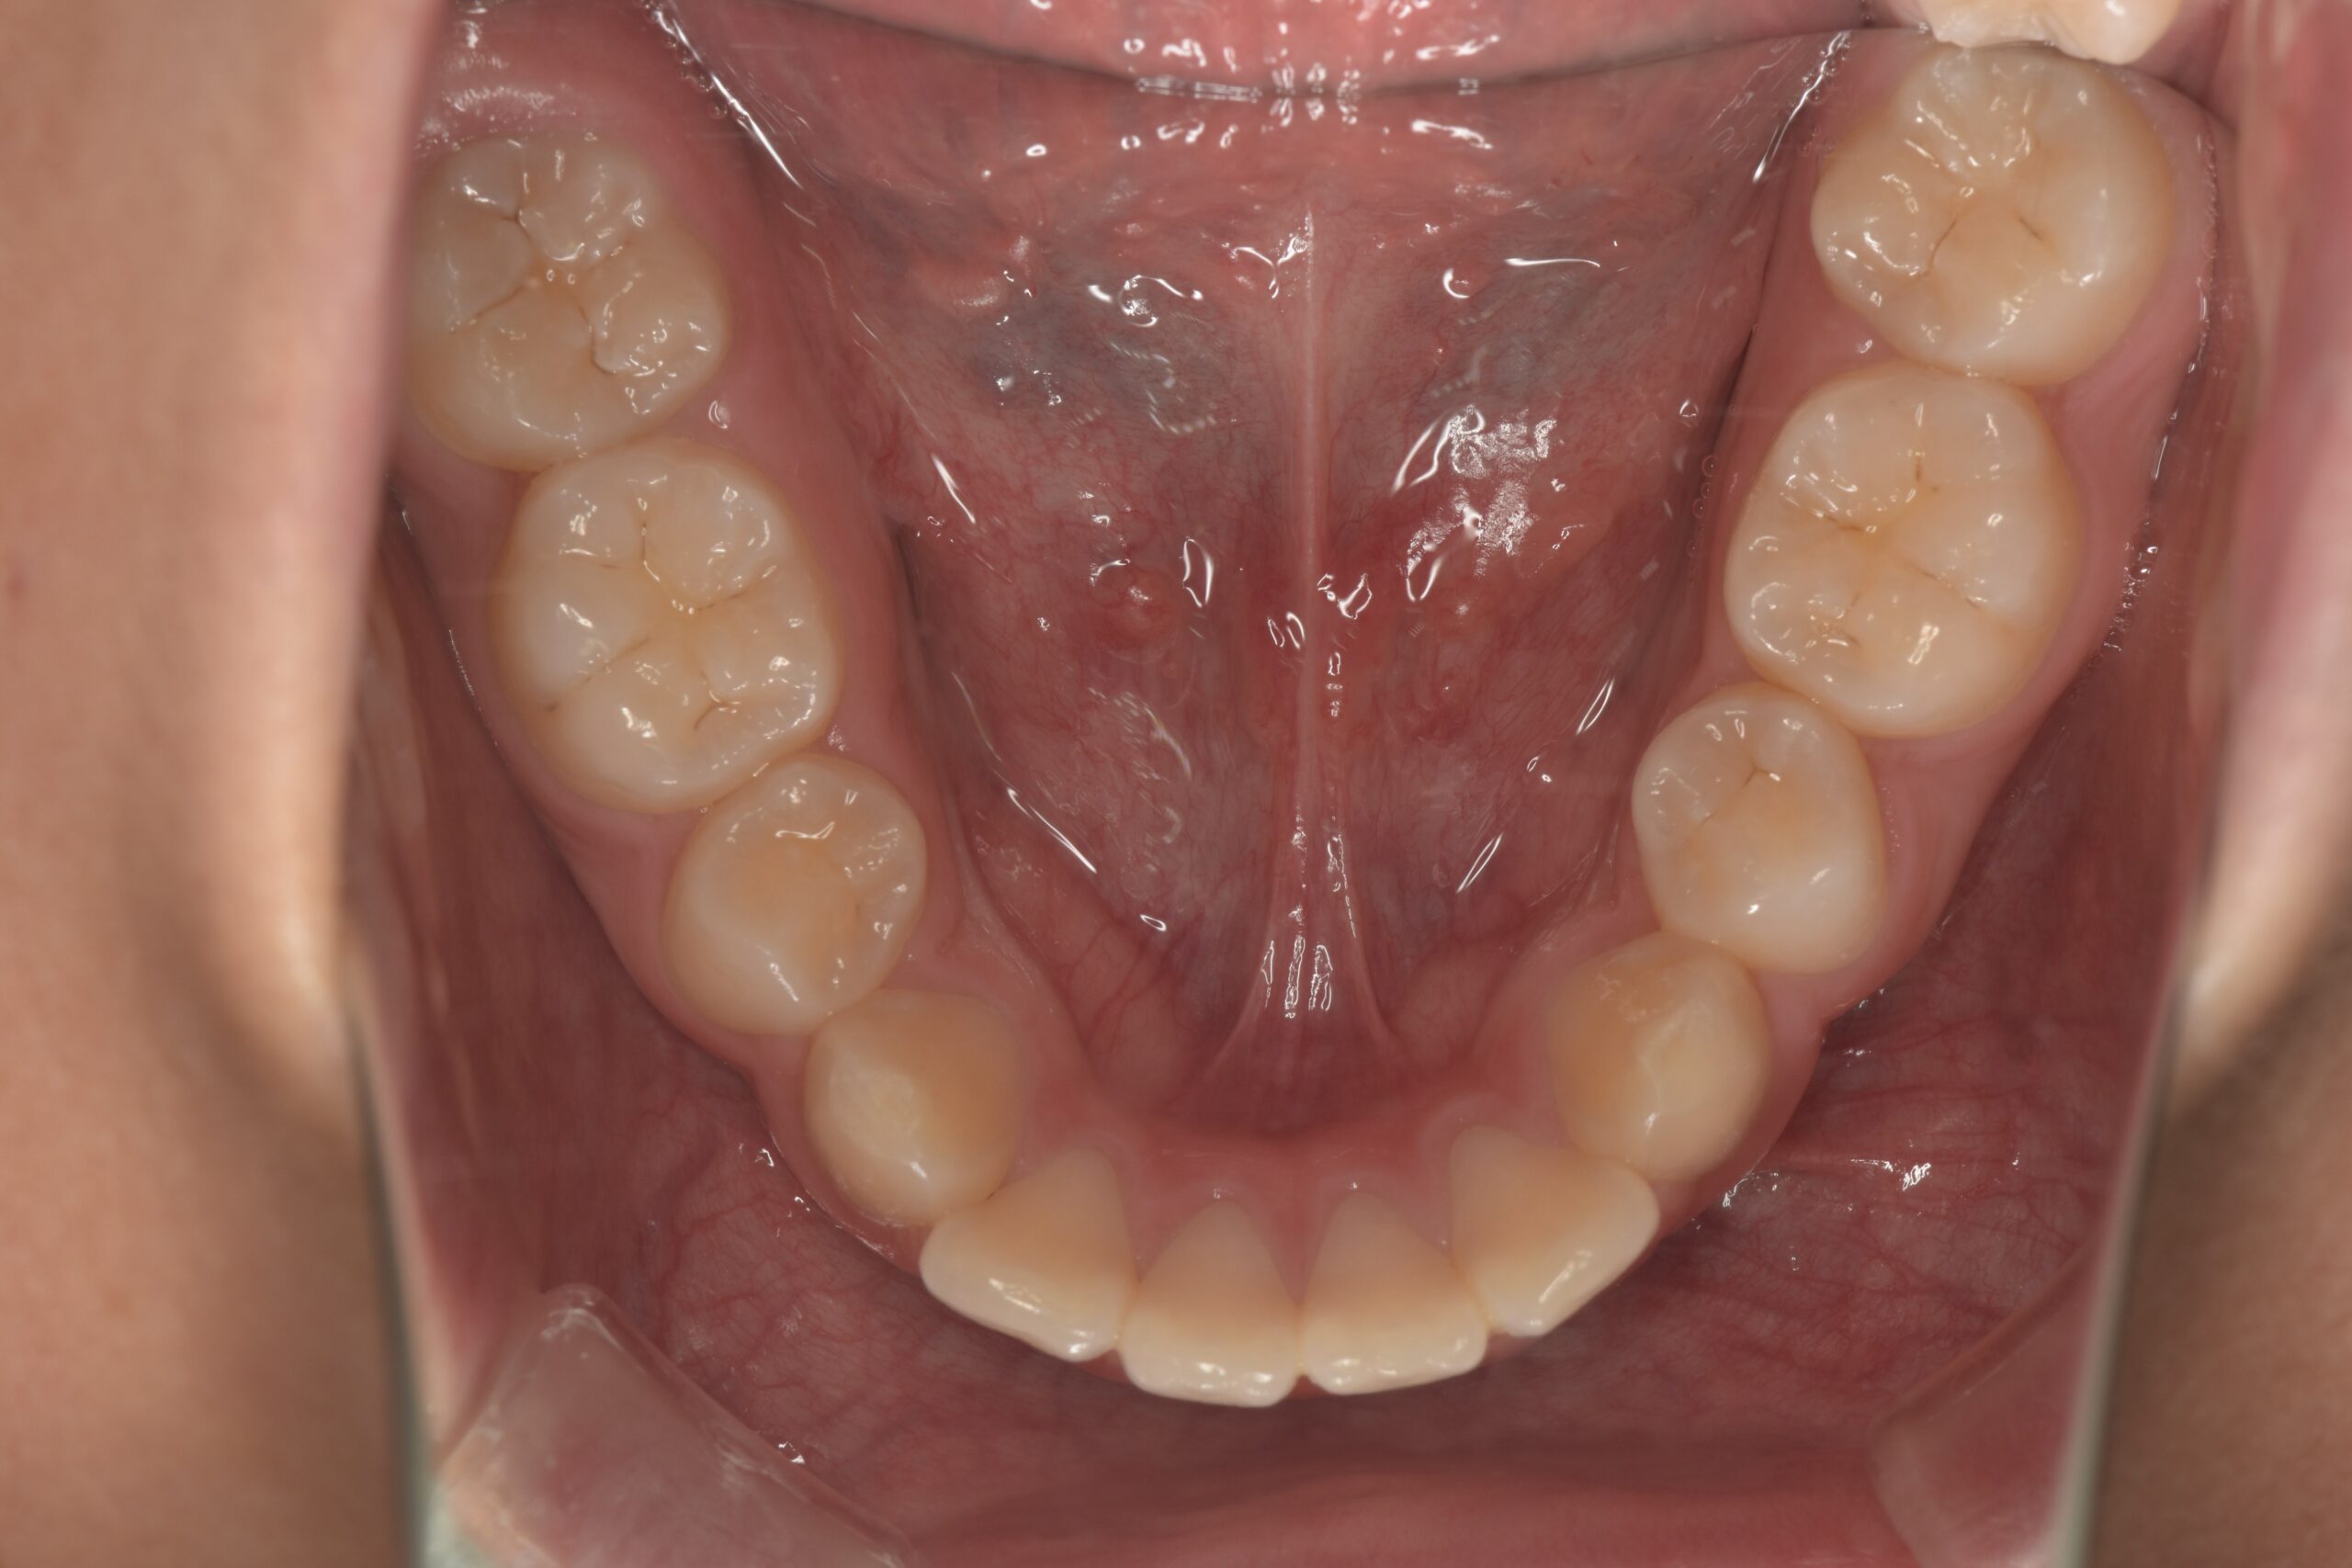

装置除去(上顎)

装置除去(下顎)